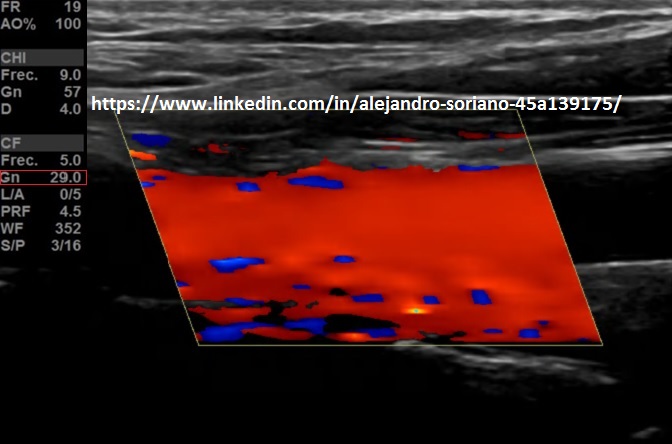

- Ganancia: sabremos que tenemos la ganancia adecuada cuando no veamos artefacto en “confeti” que se produce por exceso de ésta; y cuando veamos el vaso relleno por completo ya que veremos zonas sin pintar cuando la ganancia es baja.

- Tendremos en el mismo botón del modo de trabajo del Doppler, la capacidad de variar este valor, girando la rueda.Esto es de modo general, puede haber excepciones, según cada casa comercial.

Gain: we will know that we have the adequate profit when we do not see an artifact in «confetti» that is produced by excess of it; and when we see the filled glass completely since we will see unpainted areas when the gain is low. We will have in the same button Doppler work mode, the ability to vary this value, turning the wheel. This is generally, there may be exceptions, according to each commercial house.

- Frecuencia de repetición de pulsos (PRF) o escala de velocidades: la modificaremos en función del flujo que estemos estudiando; para flujos de alta velocidad la aumentamos para evitar “aliasing”; para bajos flujos la disminuiremos para tener mayor sensibilidad.

- Podremos variar este valor en algún ajuste ecográfico situado en nuestra botonera o menú, que se denomine, generalmente, «escala»(Flecha amarilla).

Frequency of repetition of pulses or scale of speeds: we will modify it depending on the flow we are studying; for high-speed flows we increase it to avoid «aliasing»; for low flows we will decrease it to have greater sensitivity. We can vary this value in some ultrasound adjustment located in our keypad or menu, which is called, generally, «scale» (Yellow arrow).